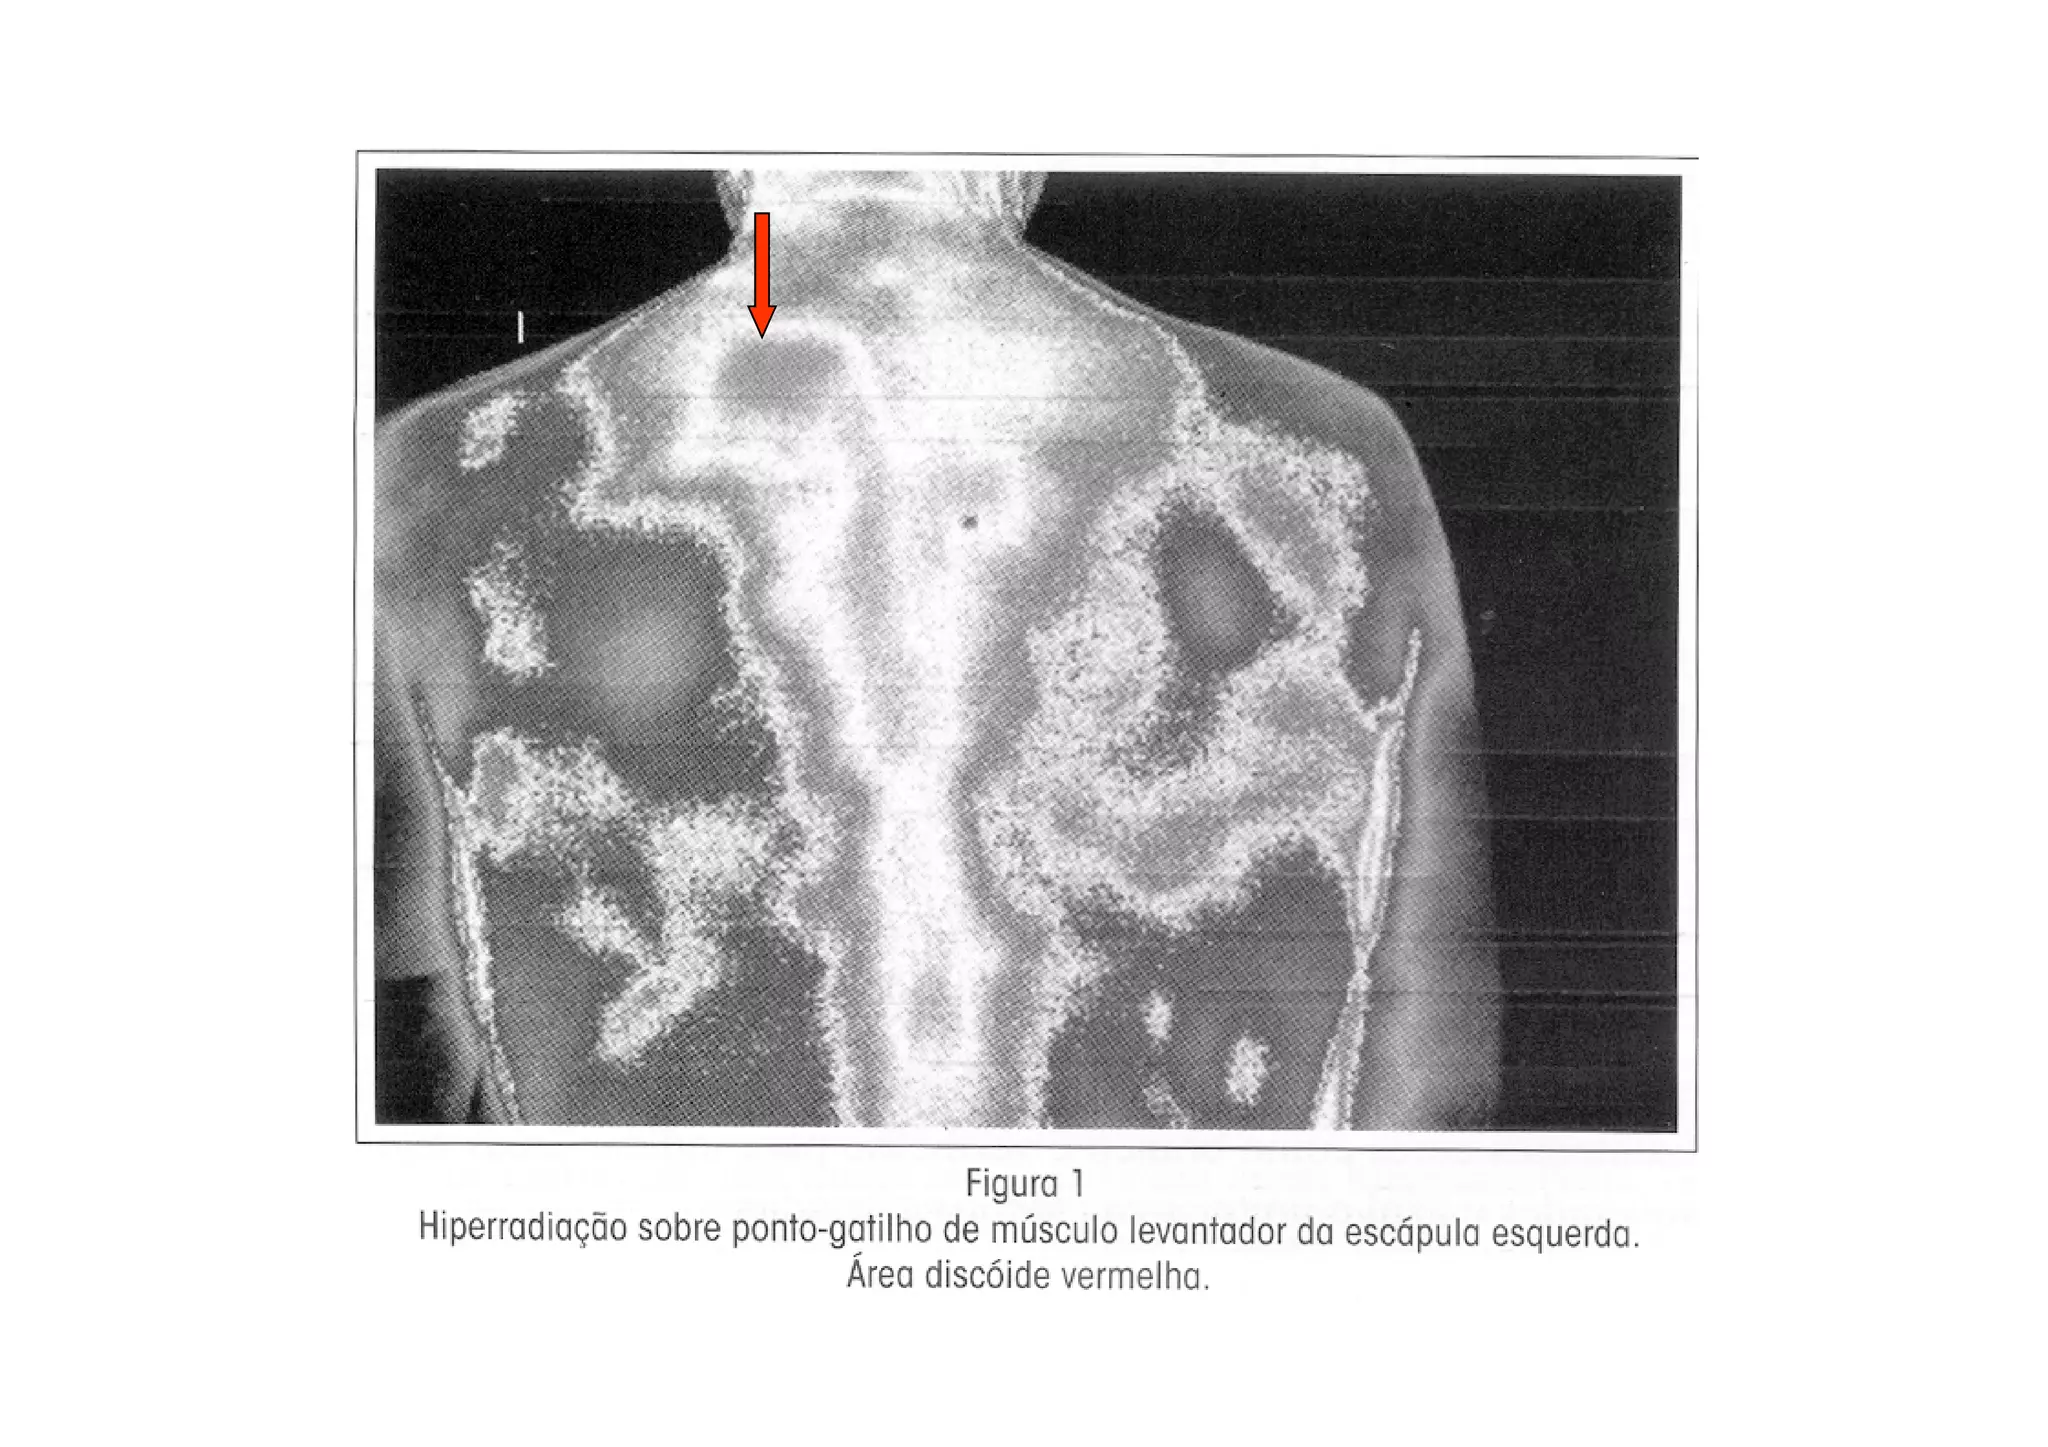

• O uso da imagem infravermelha (IR) como meio

diagnóstico da SDM e seus pontos-gatilho, constitui-

se em importante recurso objetivo

• O uso da imagem infravermelha (IR) é um recurso

objetivo na demonstração dos pontos-gatilho

miofasciais, correlatos com as queixas objetivas do

paciente.